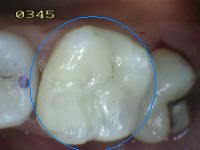

3 |

Restauración color

diente |